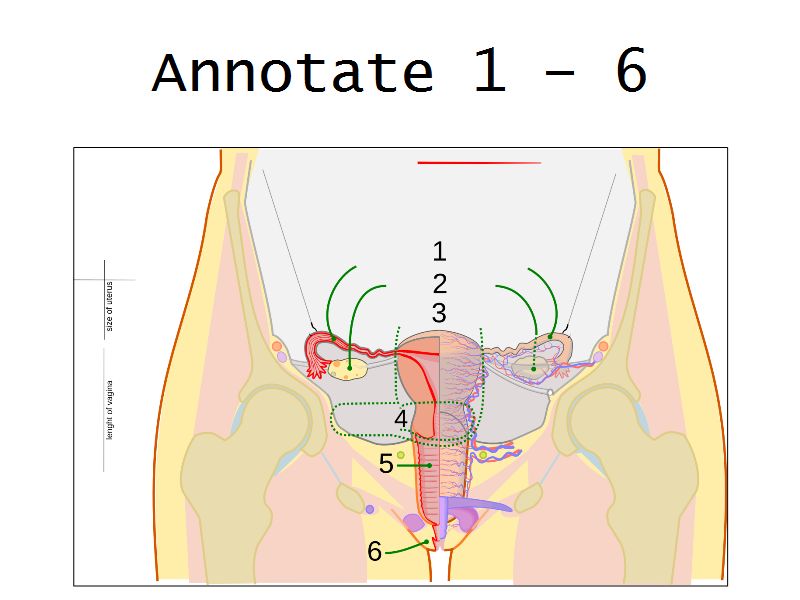

Ovaries

Slide 24

Section of the ovary

1. Outer covering. 1'. Attached border. 2. Central stroma. 3. Peripheral stroma. 4. Bloodvessels. 5. Vesicular follicles in their earliest stage. 6, 7, 8. More advanced follicles. 9. An almost mature follicle. 9'. Follicle from which the ovum has escaped. 10. Corpus luteum.